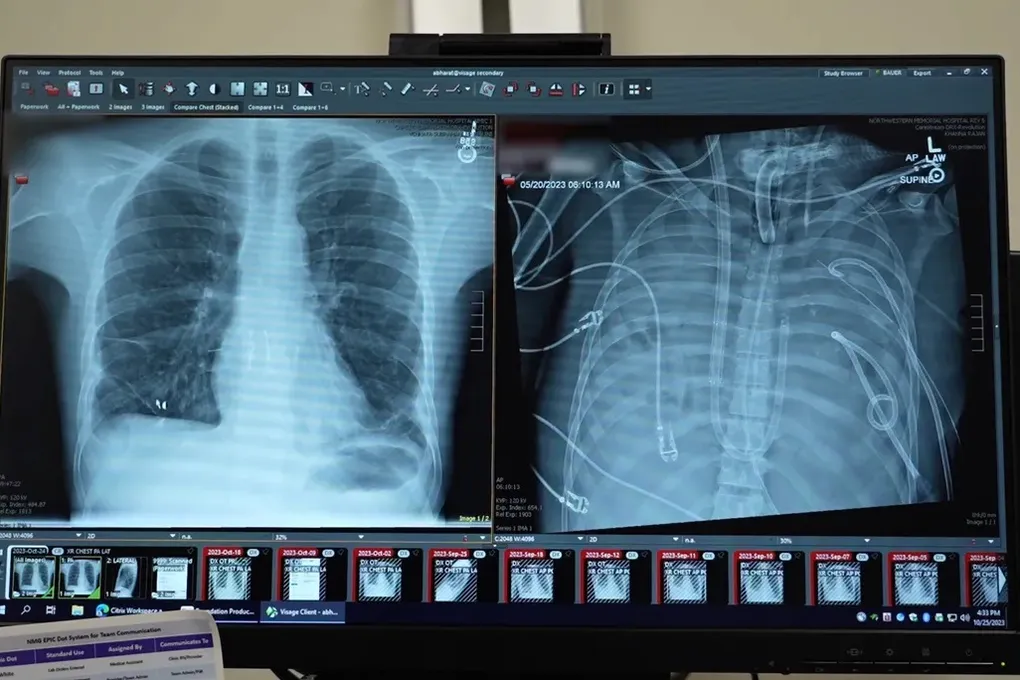

В свежей публикации в журнале Med описан невероятный случай 33-летнего пациента. Его сразил тяжелый грипп, который обернулся острым респираторным дистресс-синдромом — состояние, когда легкие просто отказываются работать. А затем подключилась бактериальная инфекция, довершив разгром тотальной пневмонией. Легкие перестали выполнять свою функцию, а вслед за ними начали сдаваться сердце и почки. Стандартное лечение уже не спасало. Тупик.

Ответом стала система полного искусственного замещения легких (Total Artificial Lung, TAL). Представьте себе внешний контур, через который пропускается кровь. Ее забирали из правых отделов сердца, прогоняли через этот аппарат, где удалялся углекислый газ и добавлялся живительный кислород, а затем возвращали обратно, в левое предсердие. Система тонко регулировала давление и поток, чтобы не убить и без того еле бьющееся сердце. В отличие от привычных аппаратов ЭКМО, которые лишь помогают легким, эта схема взяла на себя их работу целиком. И это сработало.

Именно эти двое суток, которые тело просуществовало на искусственной поддержке, стали тем самым критическим «окном». Появились донорские легкие, а состояние пациента наконец позволило рискнуть и провести двойную трансплантацию. Операция прошла успешно. Уже через неделю его отключили от аппаратов ИВЛ, а спустя два месяца он покинул больницу. Сейчас, два года спустя, его новые легкие работают как надо. Анализ же удаленных органов показал страшную картину — ткань была разрушена необратимо. Без этого отчаянного шага шансов не было.